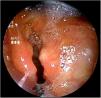

Recién nacido a término con rasgos dismórficos, ventriculomegalia bilateral y comunicación interventricular e interauricular que precisa ingreso por distrés respiratorio que requiere soporte respiratorio con ventilación mandatoria intermitente a 30rpm. Presenta episodios de tos y atragantamiento en todas las tomas. Ante la sospecha de fístula traqueoesofágica, se indica una exploración de la vía aérea mediante lente rígida de 3mm en respiración espontánea. Se observa hendidura laringotraqueoesofágica tipo III (figs. 1 y 2). Se realiza laringotraqueoplastia por abordaje abierto. En el control endoscópico a los 16 meses se observa una hendidura grado 1 que precisa de nueva cirugía. En el último control, no se observan hendiduras, con normoposición de epiglotis y aritenoides unidos por la comisura posterior (fig. 3).

La hendidura laringotraqueoesofágica se caracteriza por un defecto en la pared posterior de la laringe que puede extenderse hasta la tráquea1. Puede asociar alteraciones cardíacas, urogenitales y craneofaciales1–3. En función de su extensión, existen cuatro subtipos. Las hendiduras laringotraqueoesofágicas tipo I pueden ser manejadas de manera conservadora. Se ha descrito la corrección endoscópica del grado I y II3. Los grados III y IV precisan de cirugía abierta por la extensión del defecto1–3. El diagnóstico requiere una alta sospecha en un neonato con dificultad respiratoria, tos y atragantamiento durante las tomas. La exploración de la vía aérea permite un diagnóstico certero. Además, es útil en el seguimiento para demostrar otras alteraciones como la laringomalacia y la traqueomalacia, así como estenosis subglótica o fístulas traqueoesofágicas.